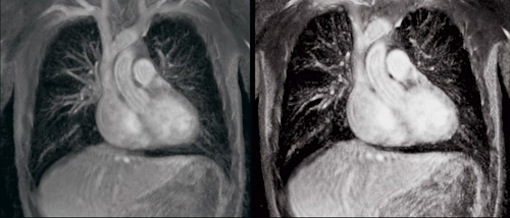

Craig Lewis was a 55-year-old, dying from amyloidosis, which causes a build-up of abnormal proteins. The proteins clog the organs so much that they stop working, according to NPR.  But after the operation, with the ‘machine’ as his heart’s replacement, Lewis’ blood continued to spin and move through his body.  However, when doctors put a stethoscope to his chest, no heartbeat or pulse can be heard (only a ‘humming’ sound)—which “by all criteria that we conventionally use to analyze patients”, Doctor Cohn said, he is dead.  This is proof that “human physiology can be supported without a pulse”.

In the short film ‘Heart Stop Beating’ by Jeremiah Zagar of Focus Forward Films, Zagar documents the process of the doctors—from cutting out the whole heart of 50 calves and replacing it with centrifugal pumps, to finally implanting it into their patient Craig Lewis.